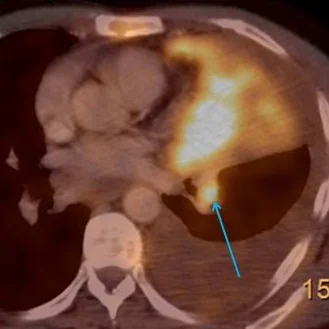

Case 2: Intense uptake on PET scan (blue arrow)